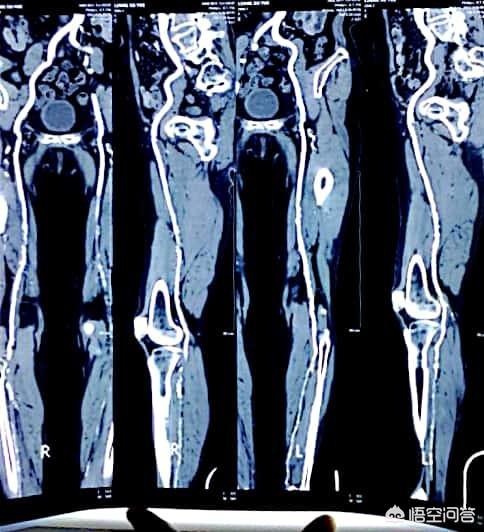

糖尿病の発生率は現在、本当に非常に高い、一般的に50歳以上、10内部の健康診断では、少なくとも1つの3つの高(高血中脂肪、高血圧、高血糖)、およびいくつかのも3つの高をすべて占めている。三高の発生と現代のペースの速い生活と人々の食習慣は大きな関係があり、次の図は糖尿病患者が登場下肢血管プラーク画像である: